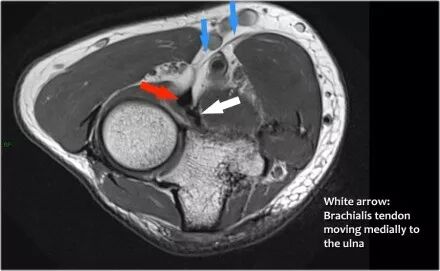

肱肌腱:肱肌起源于肱骨前部的下半部分,靠近三角肌的插入。它比二头肌更深,是一种协助二头肌弯曲肘部的增效剂。厚韧带插入尺骨冠突的前表面。

在矢状面上,比较肱肌腱(黄色箭头)和二头肌腱(红色箭头)时,注意肱肌几乎都是肌肉。它只有一个非常短的肌腱远端。